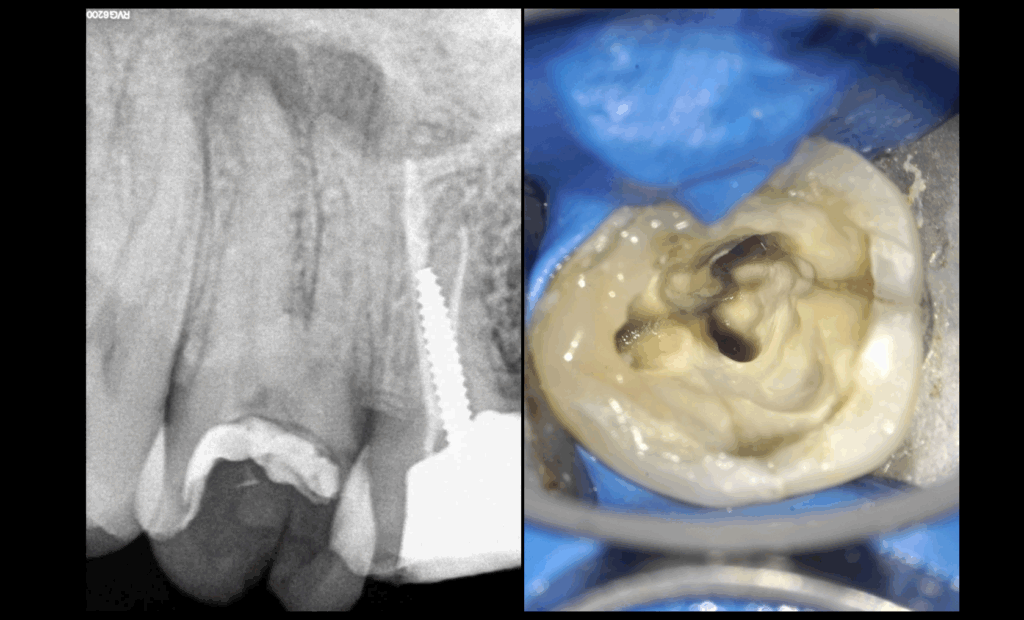

𝐏𝐮𝐥𝐩𝐞 𝐧𝐞́𝐜𝐫𝐨𝐬𝐞́𝐞, 𝐩𝐚𝐫𝐨𝐝𝐨𝐧𝐭𝐢𝐭𝐞 𝐚𝐩𝐢𝐜𝐚𝐥𝐞 𝐬𝐲𝐦𝐩𝐭𝐨𝐦𝐚𝐭𝐢𝐪𝐮𝐞.

On est en plein 𝐭𝐫𝐚𝐢𝐭𝐞𝐦𝐞𝐧𝐭 𝐜𝐚𝐧𝐚𝐥𝐚𝐢𝐫𝐞, la 𝐜𝐚𝐯𝐢𝐭𝐞́ 𝐝’𝐚𝐜𝐜𝐞̀𝐬 est terminée.

On découvre cette 𝐟𝐞̂𝐥𝐮𝐫𝐞 qui s’arrête à l’entrée canalaire. 😬

➡️ On continue tel quel.

L’extraction aurait été indiquée si la 𝐟𝐞̂𝐥𝐮𝐫𝐞 continuait dans le canal.

S’il n’y a pas de 𝐬𝐨𝐧𝐝𝐚𝐠𝐞 𝐩𝐨𝐧𝐜𝐭𝐮𝐞𝐥 𝐩𝐫𝐨𝐟𝐨𝐧𝐝 dépisté lors de la consultation, le 𝐭𝐫𝐚𝐢𝐭𝐞𝐦𝐞𝐧𝐭 𝐜𝐚𝐧𝐚𝐥𝐚𝐢𝐫𝐞 est indiqué.

🦷 Également indiqué dans ce cas-là :

Réalisation prothétique d’un 𝐫𝐞𝐜𝐨𝐮𝐯𝐫𝐞𝐦𝐞𝐧𝐭 𝐜𝐮𝐬𝐩𝐢𝐝𝐢𝐞𝐧 à type d’𝐨𝐯𝐞𝐫𝐥𝐚𝐲 ou de 𝐜𝐨𝐮𝐫𝐨𝐧𝐧𝐞 𝐜𝐨𝐥𝐥𝐞́𝐞.

❌ Contre-indication d’𝐚𝐧𝐜𝐫𝐚𝐠𝐞 𝐜𝐨𝐫𝐨𝐧𝐨–𝐫𝐚𝐝𝐢𝐜𝐮𝐥𝐚𝐢𝐫𝐞 𝐦𝐞𝐭𝐚𝐥𝐥𝐢𝐪𝐮𝐞.